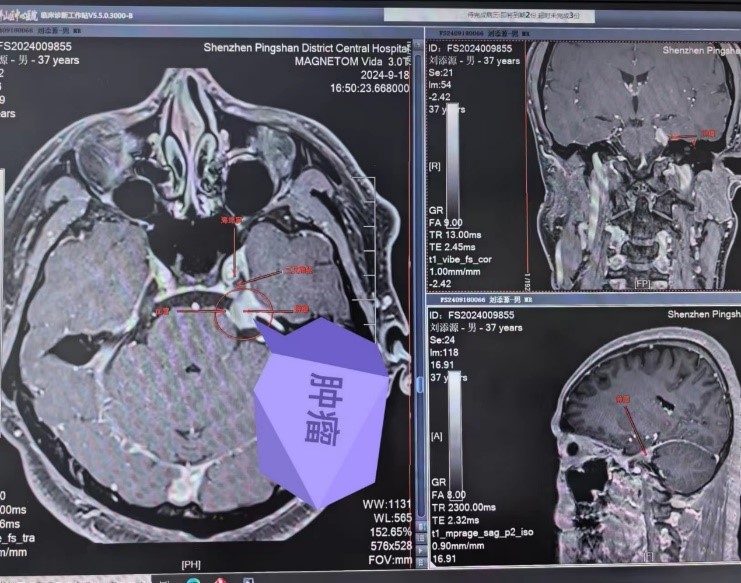

據了解,患者因出現左側面部麻木症狀已有一周時間,在外院檢查後被確診為顱內腫瘤。在焦慮和無助之際,患者慕名找到了深圳市坪山區中心醫院神經外科陳建良教授。陳教授接診後,迅速為患者進行了核磁共振增強等相關檢查。結合患者的病史、臨床症狀以及影像學檢查結果,確診為左側岩骨尖腦膜瘤,該腫瘤累及到三叉神經、海綿竇、岩靜脈及腦幹,需手術切除。

9月26日,由神經外科陳建良教授和李奇主任共同主刀,在麻醉科、手術室團隊及相關科室的緊密配合和全程監測下,藉助高倍手術顯微鏡的精準輔助,手術團隊成功地暴露了手術區域,同時小心翼翼地保護了周圍的血管、三叉神經及腦幹等重要結構。經過4個小時的努力,最終成功完整地切除了腫瘤。